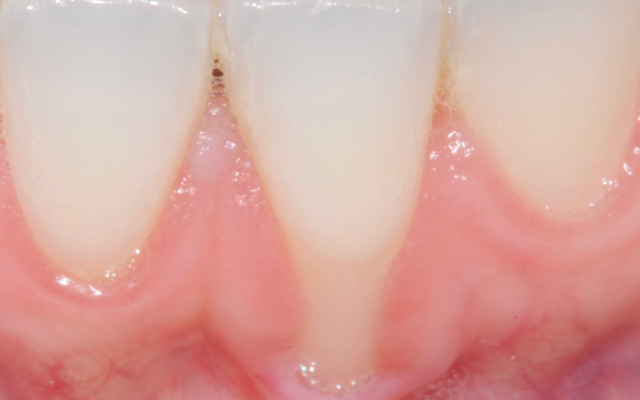

Gum grafting on teeth is a periodontal surgical procedure where the patient’s own gum is repositioned upward (Figure 12A-12B) or if the gum is thin or receded (Figure C), extra gum can be harvested from the roof of the mouth.